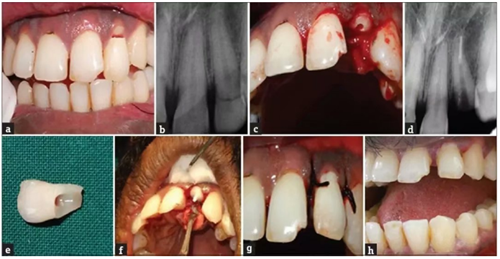

病例2

患者,男,19歲,因騎車發(fā)生事故導(dǎo)致上頜中切牙外傷??谇粰z查可見牙齒22牙冠冠部EllisⅢ級牙折,從牙冠的牙冠中1/3到舌側(cè)齦下2mm處。將牙齒折斷部分無創(chuàng)地取出并儲存在生理鹽水中,完成根管治療。如前所述,使用雙固化樹脂粘結(jié)劑通過合適的纖維樁將折斷部分的牙折片與剩余的牙齒部分重新連接。最后,復(fù)位皮瓣,縫合。

a. 術(shù)前口內(nèi)照片;b. 術(shù)前根尖片;c. 拔除牙齒折斷片;d. 根管充填;e. 牙齒折斷片;f. 折斷片再復(fù)位;g. 術(shù)后2年。